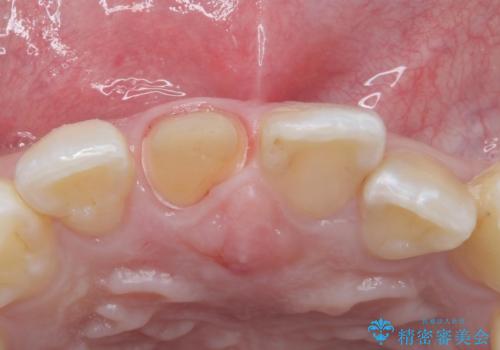

- 前歯のかぶせ物の色が気になるとのことで来院された患者様です。

セラミッククラウンで作り変えていきます。

色・形ともに改善され、大変喜んでいただけました。